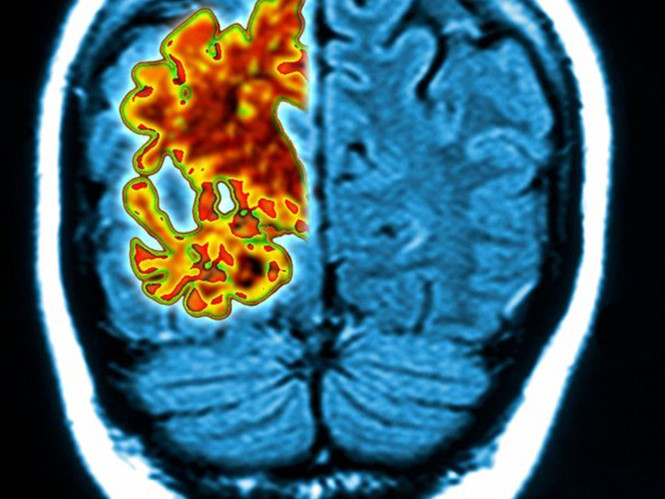

Bệnh mất trí nhớ không chỉ làm khổ người bệnh mà những người thân của họ hụt hẫng và khổ sở khi một ngày biết rằng họ bị mất trí nhớ. Thế nhưng nếu biết sớm thì vấn đề giải quyết sẽ không còn là quá khó. Một bài kiểm tra ngửi mùi đơn giản có thể giúp dự đoán chính xác bệnh mất trí nhớ trong 5 năm sau.

Một bài kiểm tra Ngửi mùi đơn giản có thể giúp dự đoán chính xác bệnh mất trí nhớ trong 5 năm sau. Bài kiểm tra này đã được các nhà nghiên cứu ở Mỹ thử nghiệm trên 3.000 người ở độ tuổi 57 đến 85.

Giáo sư Pinto nói trên Tạp chí của Hội lão khoa Mỹ rằng mất đi giác quan nhận biết về mùi là một dấu hiệu rõ ràng cho thấy đang có một sự tổn thương nào đó. Bài kiểm tra ngửi mùi đơn giản có thể nhanh chóng giúp xác định được ai là đối tượng nguy cơ cao.